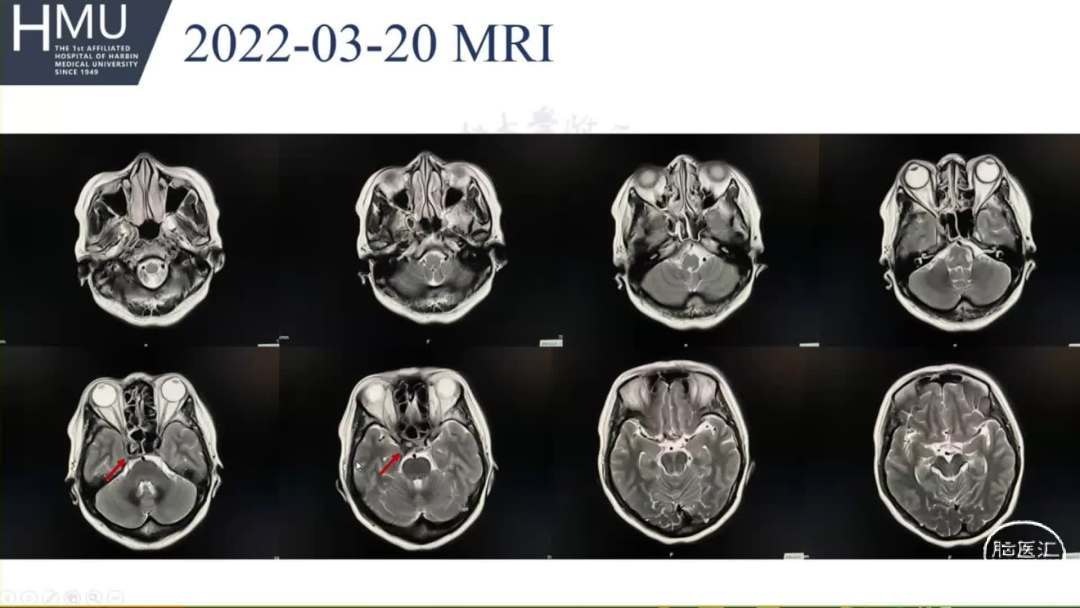

●女,52岁,因“头痛4日,右侧眼脸下垂1日” 入院

入院前4日无诱因出现后枕部头痛,呈针刺样持续性疼痛,入院前1日,出现右眼睑下垂伴眼球胀痛

神清语明,右眼球固定,双侧瞳孔

左:右=2.5mm:5mm,右眼光反射消失,颈强阳性。